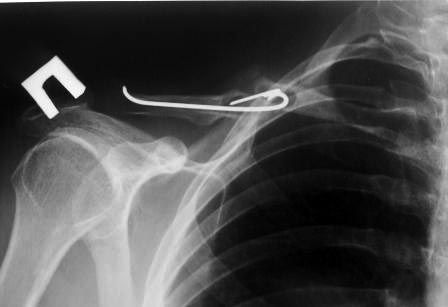

УУважаемые коллеги. Обратился пациент 29лет, оперирован в 2007 г. в

Республиканском центре по поводу перелома ключицы и/м спицей,

после несращения повторно оперирован в 2008 году, со слов больного

освежение и повторно фиксация спицами, и обратился только через 6 лет,

активные и пассивные движения в правом плечевом суставе в полном объеме,

беспокоит только слабость при поднятии тяжести и подвижность в с/з

ключицы. Р-снимок прилагается.Честно признаться, пока не знаю, что

делать, имеются обычные пластины из ЦИТО, спицы, может, краевая резекция

до появления «росы» дефект заполнить спонгиозной костью, фиксация и/м

двумя спицами, загнуть оба конца спицы с компрессей, или пластина…или

вообще не трогать.